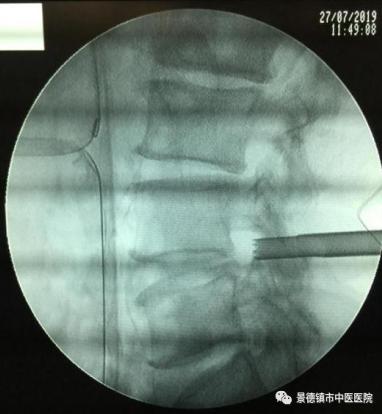

精準(zhǔn)定位,直達(dá)靶點